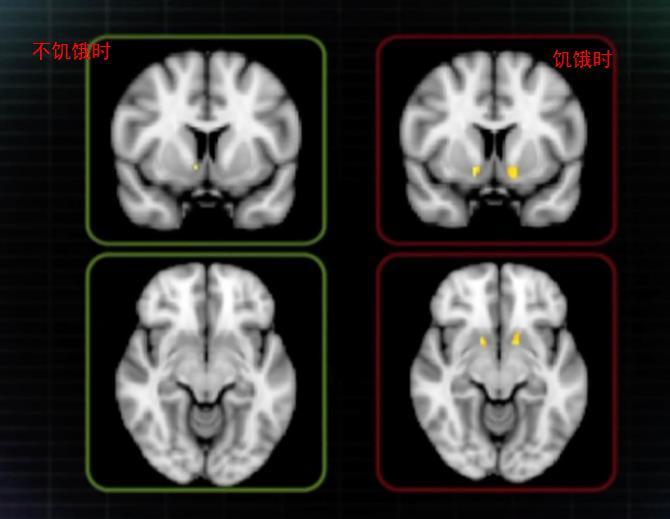

人在饥饿的时候,对于食物的渴望会更加强烈,当我们不吃早饭的时候,我们一看到高热量的食物相对于低热量的食物是更加活跃的,就会觉得快餐炸鸡比青菜馒头有食欲。

饿的时候,大脑会想方设法的让你对高热量产生欲望,从而引发我们对于食物的强烈的渴望,意志力薄弱的人就会很难招架了。